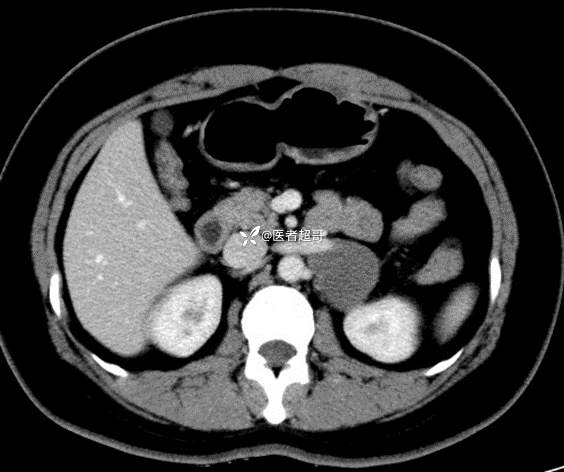

病例【影诊笔记711】女,23岁,体检发现左侧肾上腺占位,有病理,请赏析~~~

女,23岁,体检发现左侧肾上腺占位